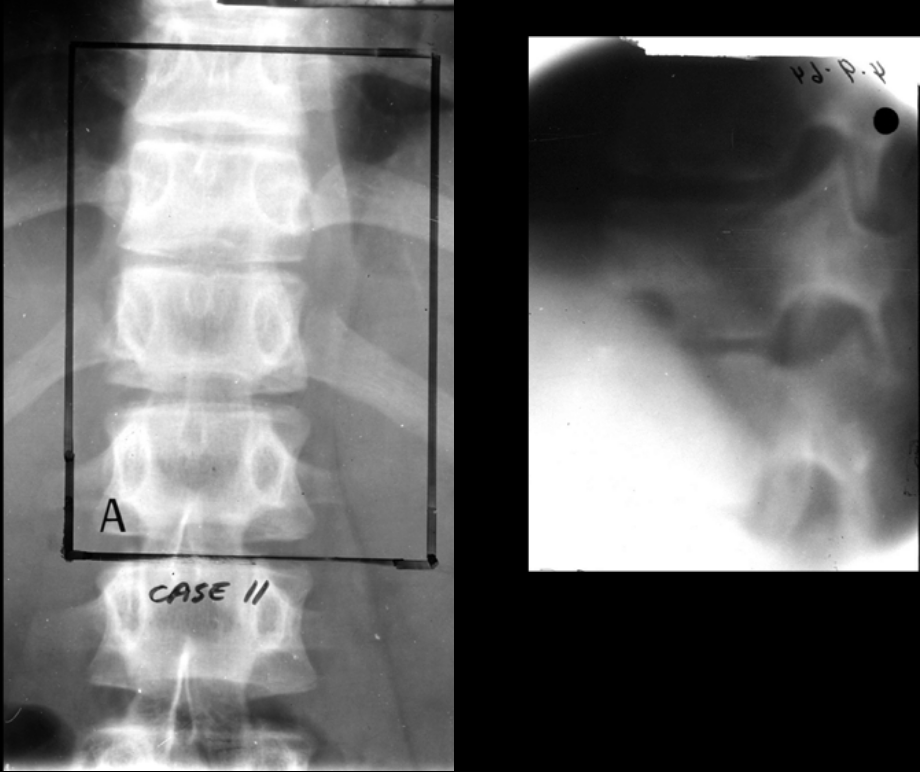

Q

7-year-old male with leg pain, swelling, and a fever has normal x-rays.

This is a T1 fat suppression MRI with contrast.

What is the diagnosis?

A

Osteomyelitis

medullary cavity infection with cloaca